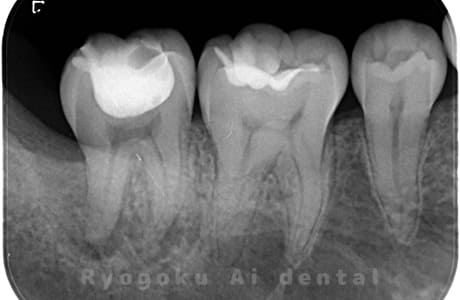

Case02

-

- 原因

- 慢性根尖性歯周炎

- 治療期間

- 3ヶ月

- 治療内容

- マイクロエンド

- 治療費用

- 121,000円

噛むと痛みが出る、とのことで来院した患者様です。他院での根管治療を終えてましたが、根尖病変を認めるため、マイクロエンドを行いました。

<リスク・副作用>

術後は痛み、腫れ、痺れなどの副作用が生じる場合があります。症状が再発する可能性があります。